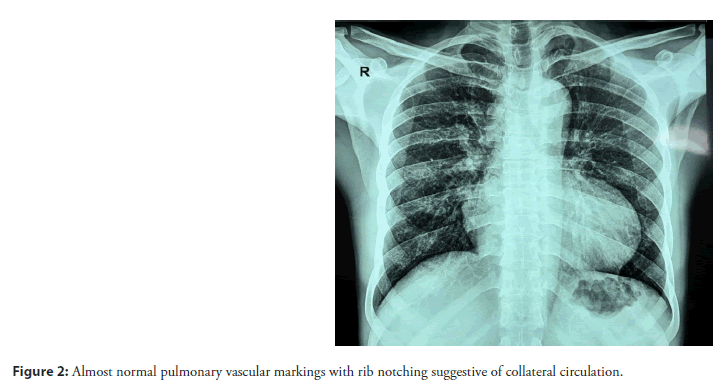

Electrocardiogram demonstrated right ventricular hypertrophy. Chest radiograph revealed almost normal pulmonary vascular markings with rib notching suggestive of established collateral circulation (Figure 2).